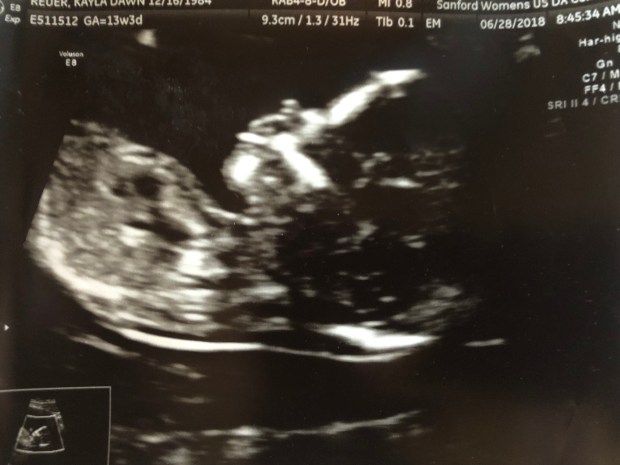

Then came the fun part, our 15-20 minutes looking at our baby!

But it was there instantly!  I didn’t need to search for the beautiful flicker because it showed up right on queue, plain as day, and lit up the screen for me!  Throughout the entire scan, it was almost all I could look at, that marvelous flickering organ!  Our baby continued to have a pulse and be alive and that was my biggest concern that day!

Baby was moving around like crazy.  They alway are moving around like crazy, at every scan we’ve had they are an active little bean!  What does this mean for the future?!?!